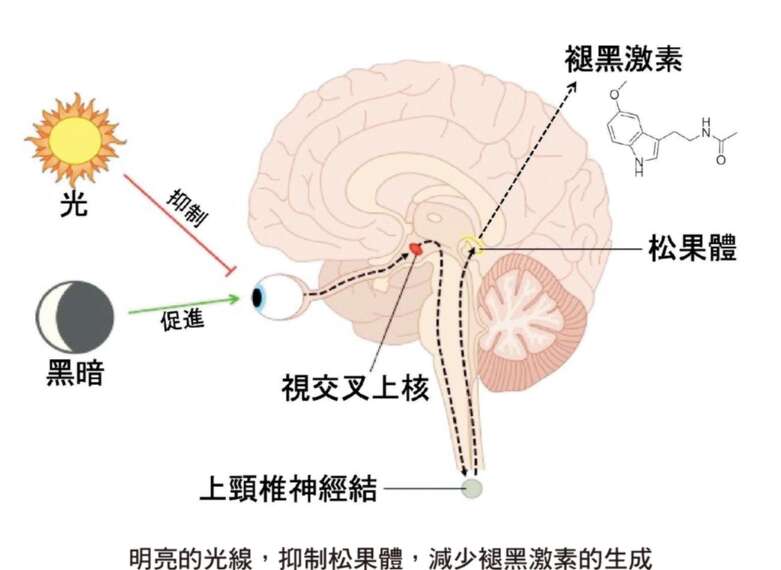

褪黑激素可以說剛好和皮質醇作用的時間相反,是在太陽下山後,9點開始分泌,夜裡11〜12點到高峰,到天亮時,已經幾乎消失。其實,褪黑激素的水平和我們的體溫變化趨勢是剛好相反的。到了夜晚,褪黑激素上升,而核心體溫逐漸下降,身體的作用程序也開始慢了下來。也就是說,我們要入睡,無論內分泌和全身的生理與代謝程序,都要同步朝向睡眠的方向前進。

05 太陽光:改變日週期的鑰匙

最好的一個改變日週期的實例,也就是透過光線。尤其明亮的光線,效果更為明顯。

我們本來就離不開太陽的光線,只要接觸太陽光,自然可以調整我們的步調。甚至,如果要到不同時區出差或剛回來,在一開始的幾天或幾星期多曬太陽,就可以把時差整個重新調整過來。我常提醒出差的朋友,最好撥出一點時間,尤其在中午太陽最強的時候,一定要出去曬曬太陽,讓身體可以和當地的時間重新對時。

為什麼白天的太陽光可以有那麼大的作用?我在這裡,想多做一點說明。

回到陽光的作用,舉例來說,在眼睛的視網膜上有一些神經,直達啟動日週期的中樞,也就是前面提過的視交叉上核。這些視神經上有一種色素,叫做黑視素(melanospin),對波長較短的藍光特別敏感。這種藍光特別能活化視交叉上核,而視交叉上核又直接通往松果體,去抑制松果體的活性,不讓它產生褪黑激素。(前面提過,褪黑激素會讓人有睡意,體溫下降,讓身體知道該睡覺了。)

一個人如果希望好睡,那麼睡前少看螢幕,確實對入睡是有幫助的。一來,螢幕產生的藍光,降低褪黑激素分泌的效果相當直接。此外,我們也都能體會到,生活中無所不在的資訊,對頭腦造出來的刺激,可能比藍光的影響遠遠更大。

無論如何,如果希望好睡,睡前最好給自己一個空檔,遠離資訊,也遠離藍光。這麼做,不只能改善睡眠,也可以保護眼睛和視力。畢竟藍光是能量最強的可見光,接收太多藍光,會傷害你的視網膜而可能導致黃斑部病變。

當然,藍光並不是一無是處。大多數的人類,還是日行性的動物。白天的光線(尤其裡頭含的藍光)抑制松果體分泌褪黑激素的作用,讓我們比較不容易打瞌睡。從生理調控的角度來談,這個抑制的過程,其實也就等於在重新設定醒睡的週期。白天把褪黑激素抑制下來,到晚上再來釋放,讓身體去好好睡一覺。

藍光對身體有種種的作用,而其中之一就是帶來身心週期的重整。然而,自然的光線帶著完整的光譜,對我們有最好的作用。平時,我也建議朋友在早上和下午多曬點太陽,白天自然不那麼容易覺得疲憊,晚上也就自然想睡。